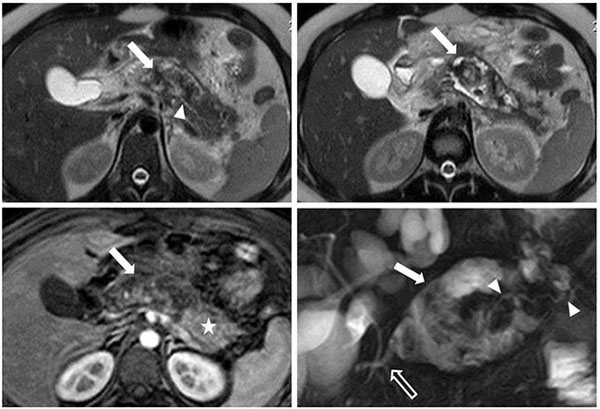

Se presenta un caso de un varón de 24 años de edad cursando una pancreatitis aguda necrohemorrágica, donde en el estudio tomográfico inicial se detectó un área de necrosis a nivel del cuerpo pancreático menor a ⅓ del parénquima con una pequeña colección post-necrótica aguda asociada. Se realizó una resonancia magnética (RM) de control unas 5 semanas luego de comenzado el cuadro, donde se observó una colección heterogénea a nivel del cuerpo del páncreas por presencia de debris, compatible con un área de necrosis encapsulada o walled off necrosis (WON). La porción caudal del páncreas presentaba adecuado realce post-contraste y en las secuencias de colangio-RM se identificó un páncreas de configuración divisum como probable causal del cuadro. Además, pudo demostrarse la relación del conducto pancreático principal con la colección, a la cual ingresaba en un ángulo de 90° (Fig. 1). Con esos hallazgos se planteó como posibilidad una desconexión del ducto pancreático principal.

Cortes axiales ponderados en T2 que muestran una colección heterogénea atribuible a una necrosis encapsulada a nivel del cuerpo del páncreas (flecha blanca) y la relación de la colección con el conducto pancreático principal (cabeza de flecha). (C) Axial ponderado T1 FS con gadolinio, muestra tejido pancreático viable con adecuado realce post-contraste en la porción caudal del páncreas (estrella) y la colección a nivel del cuerpo pancreático (flecha blanca). (D) Colangio-RM donde se observa la relación del conducto pancreático principal (cabezas de flecha) con la colección a nivel del cuerpo del páncreas (flecha blanca), a la cual ingresa en un ángulo recto. Se observa además un ducto pancreático de configuración divisum como probable causal (flecha hueca).